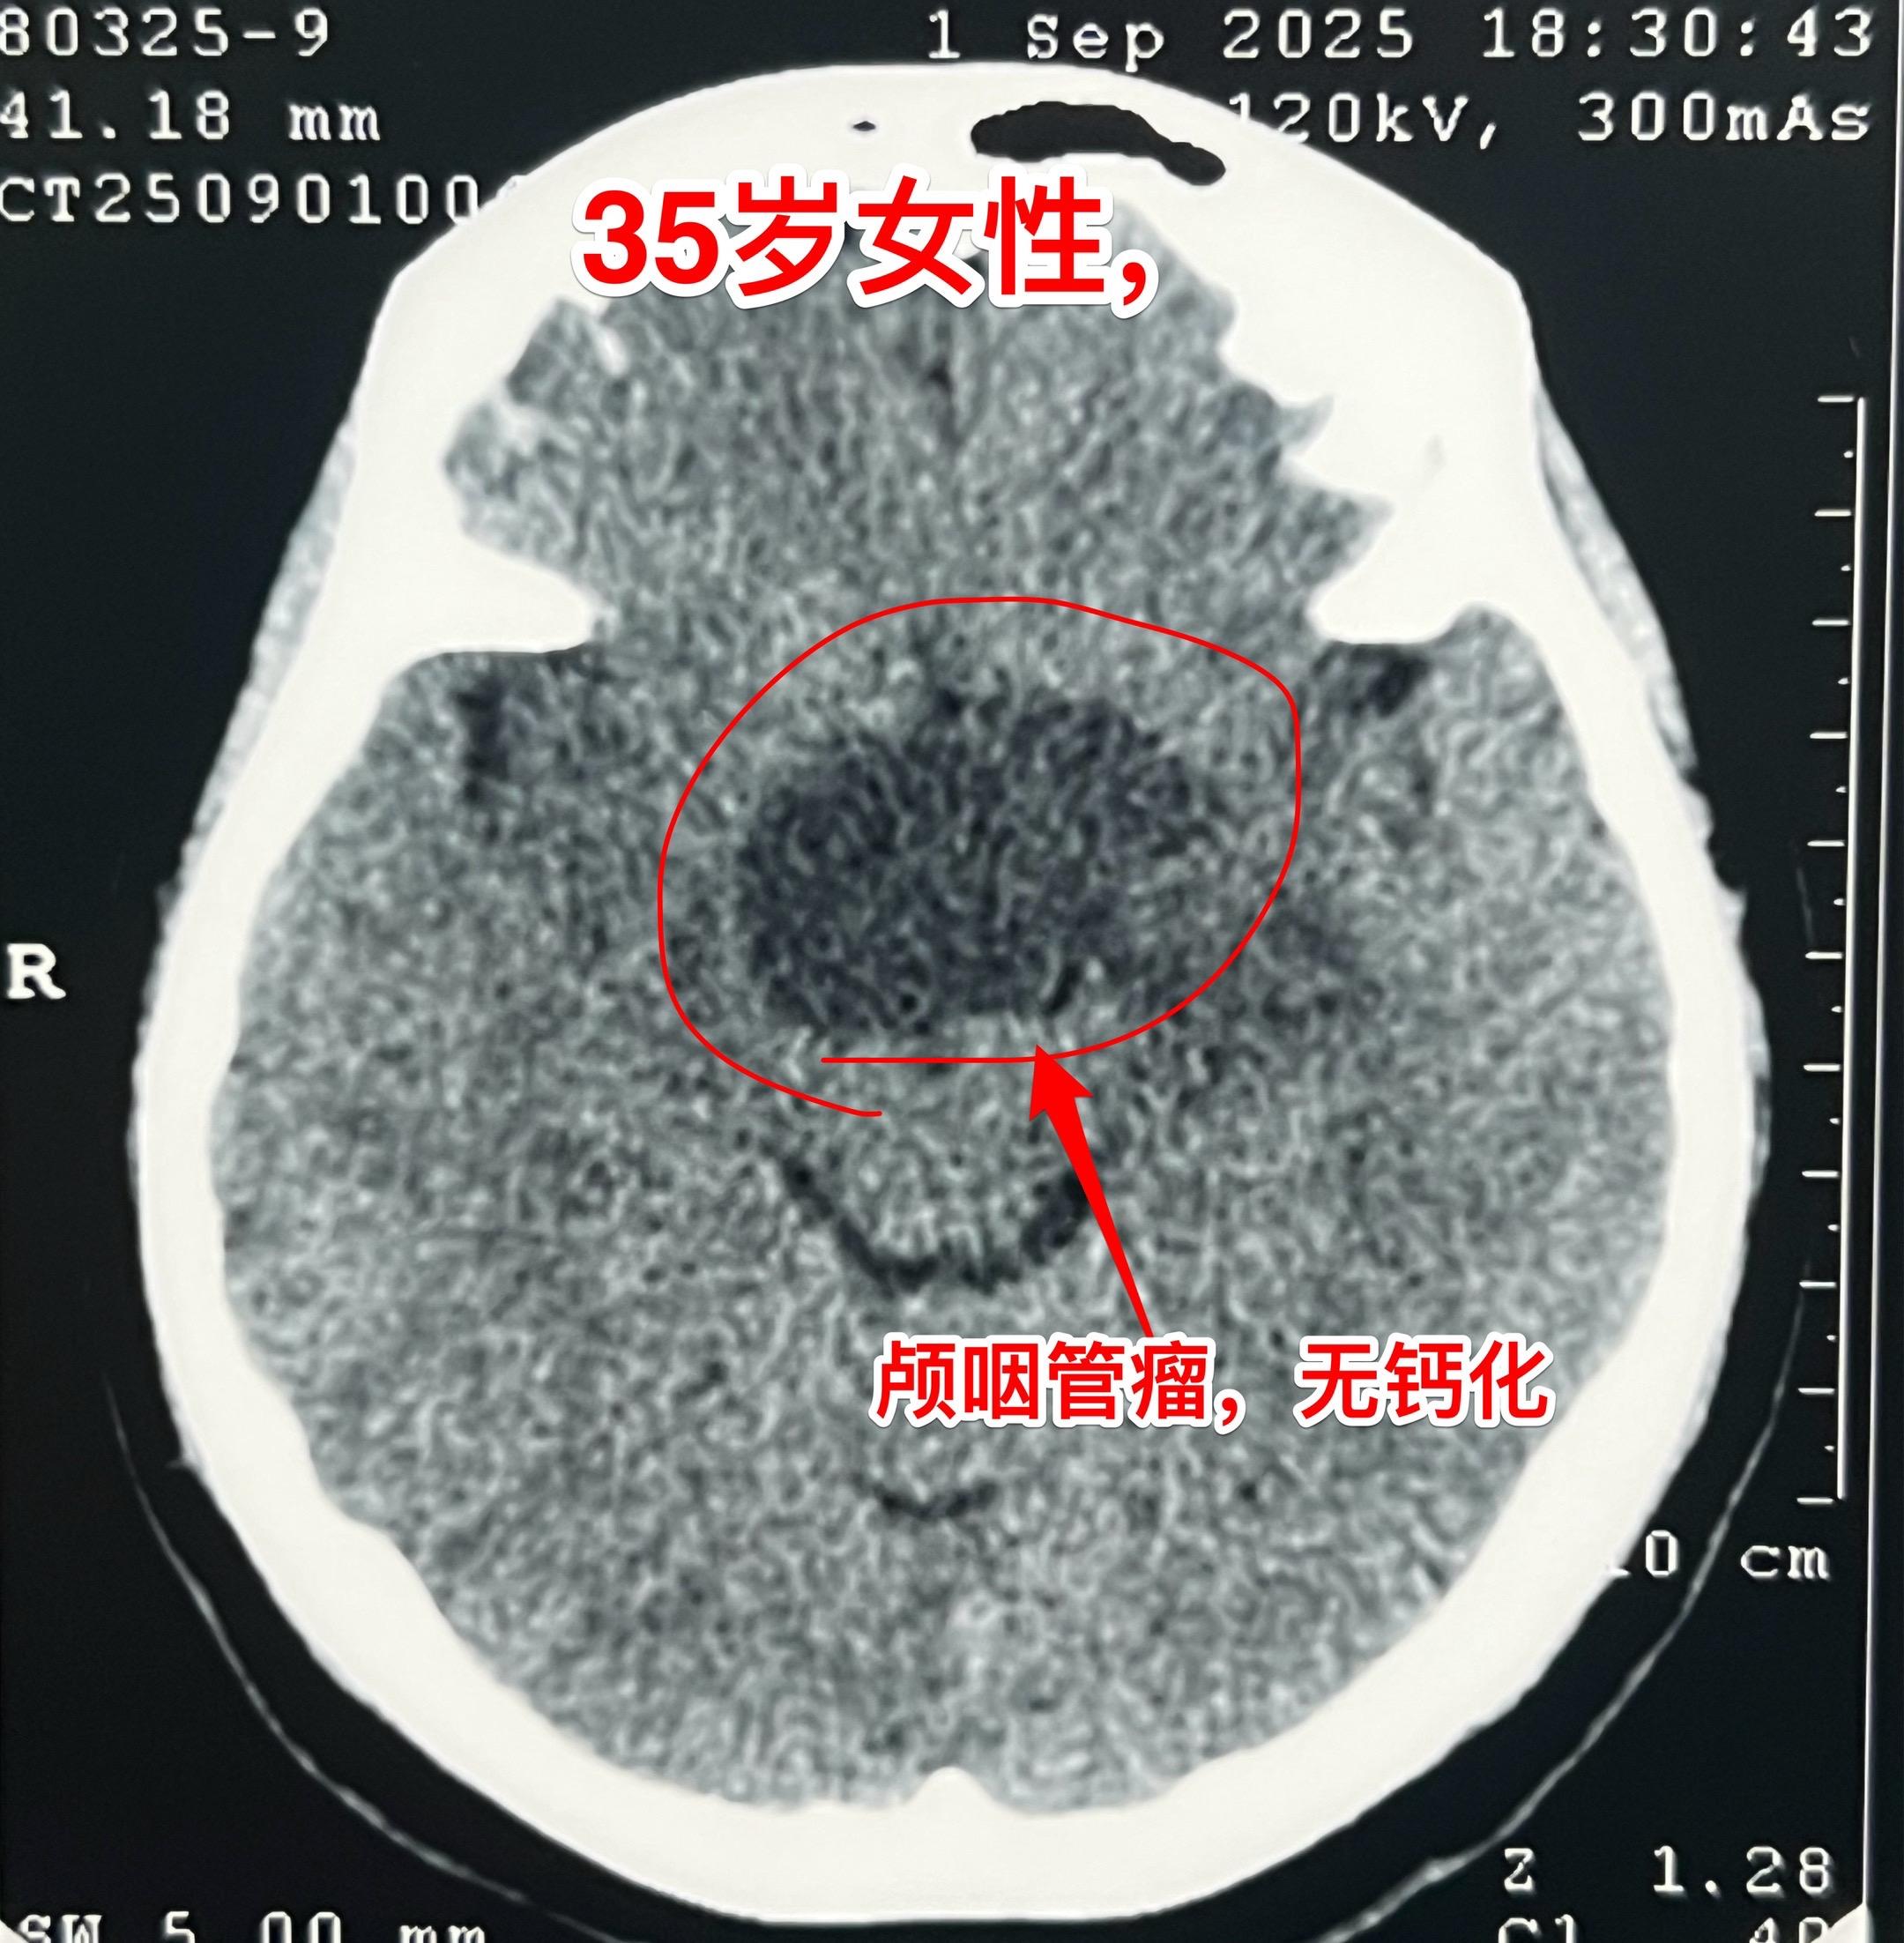

颅咽管瘤的症状科普。之前我多次讲过颅咽管瘤的症状,结合这个病人再说一次。 这个35岁女性在2025年8月发现了颅咽管瘤。 她两年前最开始出现生理周期紊乱、停经,这是下丘脑-垂体受损伤导致的内分泌系统功能障碍的表现。 一年前患者出现视力下降,越来越严重,一直到没有有效视力了才去就医,才发现这个颅咽管瘤。这是视神经-视交叉受到肿瘤压迫造成的。 在视力下降的同时病人出现长胖,体重显著增加。这也是下丘脑受损的表现。 病人在就诊